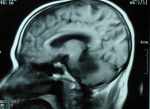

右側(cè)聽(tīng)神經(jīng)瘤手術(shù)操作個(gè)人經(jīng)驗(yàn)小結(jié) 關(guān)鍵疾病:右側(cè)聽(tīng)神經(jīng)瘤雙側(cè)硬膜下積液 現(xiàn)病史【一般資料】 男性,72歲, 【主訴】 走路不穩(wěn),15天。 【現(xiàn)病史】患者緣于4年前逐漸出現(xiàn)右側(cè)耳鳴、耳聾;2年前耳聾加重,耳鳴消失。3個(gè)月前出現(xiàn)頭昏、惡心、進(jìn)食減少。半個(gè)月前發(fā)現(xiàn)走路不穩(wěn),向左側(cè)傾倒,在當(dāng)?shù)蒯t(yī)院行MRI檢查,見(jiàn)右側(cè)橋小腦角區(qū)占位病變,考慮為聽(tīng)神經(jīng)瘤,今為進(jìn)一步治療來(lái)我院。發(fā)病以來(lái)無(wú)面部麻木、偏癱,無(wú)飲水嗆咳及聲音嘶啞。未進(jìn)行過(guò)化療。否認(rèn)高血壓糖尿病史 【既往史】既往無(wú)特殊。 【查體】 T:36.1℃,P:74次/分,R:20次/分,BP:130/80mmHg。神清,對(duì)答好,...